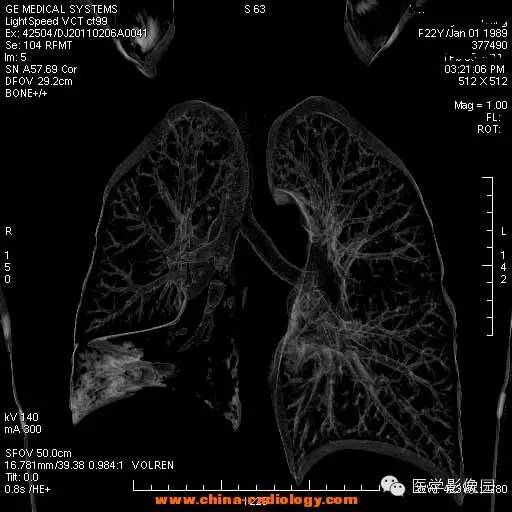

【病例】支气管异物1例CT影像表现

女,22岁,食用开心果后咳嗽不适。

管支气管异物是临床常见急症。异物可存留在喉咽腔、喉腔、气管和支气管内,引起声嘶、呼吸困难等,右支气管较粗短长,故异物易落入右主支气管。75%发生于2岁以下的儿童。CT三维重建清晰直观的显示异物的大小、位置,并能观察肺组织内是否有病变。